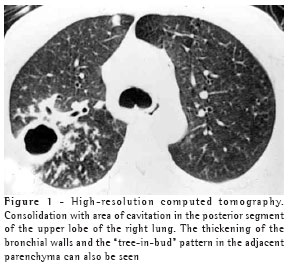

The most frequent finding in the imaging, present in the seven patients, was ill-defined consolidation (Figures 1, 2, 3 and 4). Five of patients presented air bronchogram, principally at the periphery of the lesion. In three cases, the consolidation was organized in the form of a mass. In six of the seven patients, irregular areas of cavitation were observed within the consolidations. Multiple cavitations were seen in five patients, and a singular cavitation was observed in one patient. In the patient presenting no cavitation, there were hypodense areas suggestive of necrosis (Figure 5). Only one of the patients presented air-fluid levels within the cavities.

None of the other findings described in the literature (pulmonary coin lesion, pleural effusion, pneumothorax, lymph node enlargement and soft tissue involvement) were observed in any of the patients.